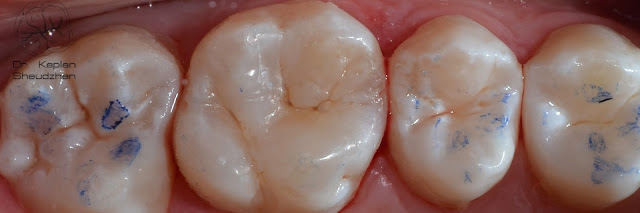

Каплан Опубликовано 26 марта, 2017 Автор Поделиться Опубликовано 26 марта, 2017 Давно что-то ничего не публиковал тут... Так что простите за спам )) все выполнено одним цветом GC Essentia Universal. 3 Ссылка на комментарий

Каплан Опубликовано 26 марта, 2017 Автор Поделиться Опубликовано 26 марта, 2017 2 часа от вкола. Не идеально. валики надо чуть дисками подправить. оставили коррекцию на след. визит, когда будем лечить 5 и 7. 2 Ссылка на комментарий